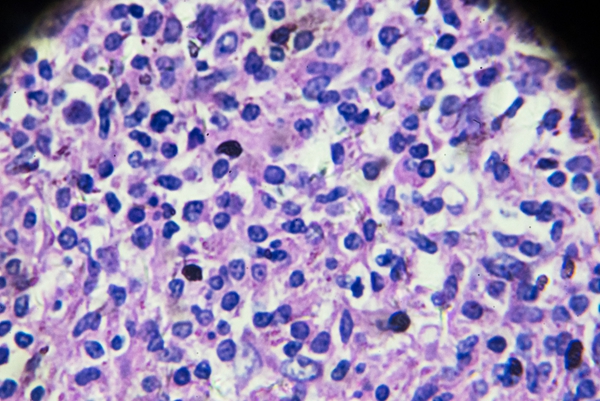

淋巴结肿大:常见于颈部、腋窝和腹股沟等部位,淋巴结质地较硬,无压痛,可活动。